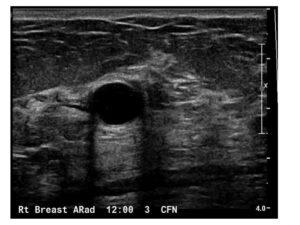

This course covers the sonographic evaluation of benign and malignant breast masses, focusing on differentiating simple cysts, complex masses, and solid tumors. Gain insights into the ultrasound features of common benign conditions like simple cysts, fibroadenomas, and lipomas, as well as how to recognize suspicious characteristics that could indicate malignancy, including irregular margins, posterior acoustic shadowing, and microcalcifications. The course also discusses advanced topics such as complex masses, intraductal tumors, and lymph node assessments, providing a thorough understanding of how ultrasound is used to guide diagnosis, biopsy decisions, and treatment planning for breast cancer.